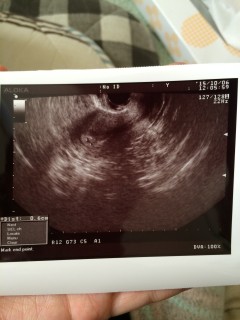

体外受精で双子を妊娠しました。 12.3㎜と9.1㎜かな? びっくりしましたが、ふたりとも無事に産まれてきて欲しいです。